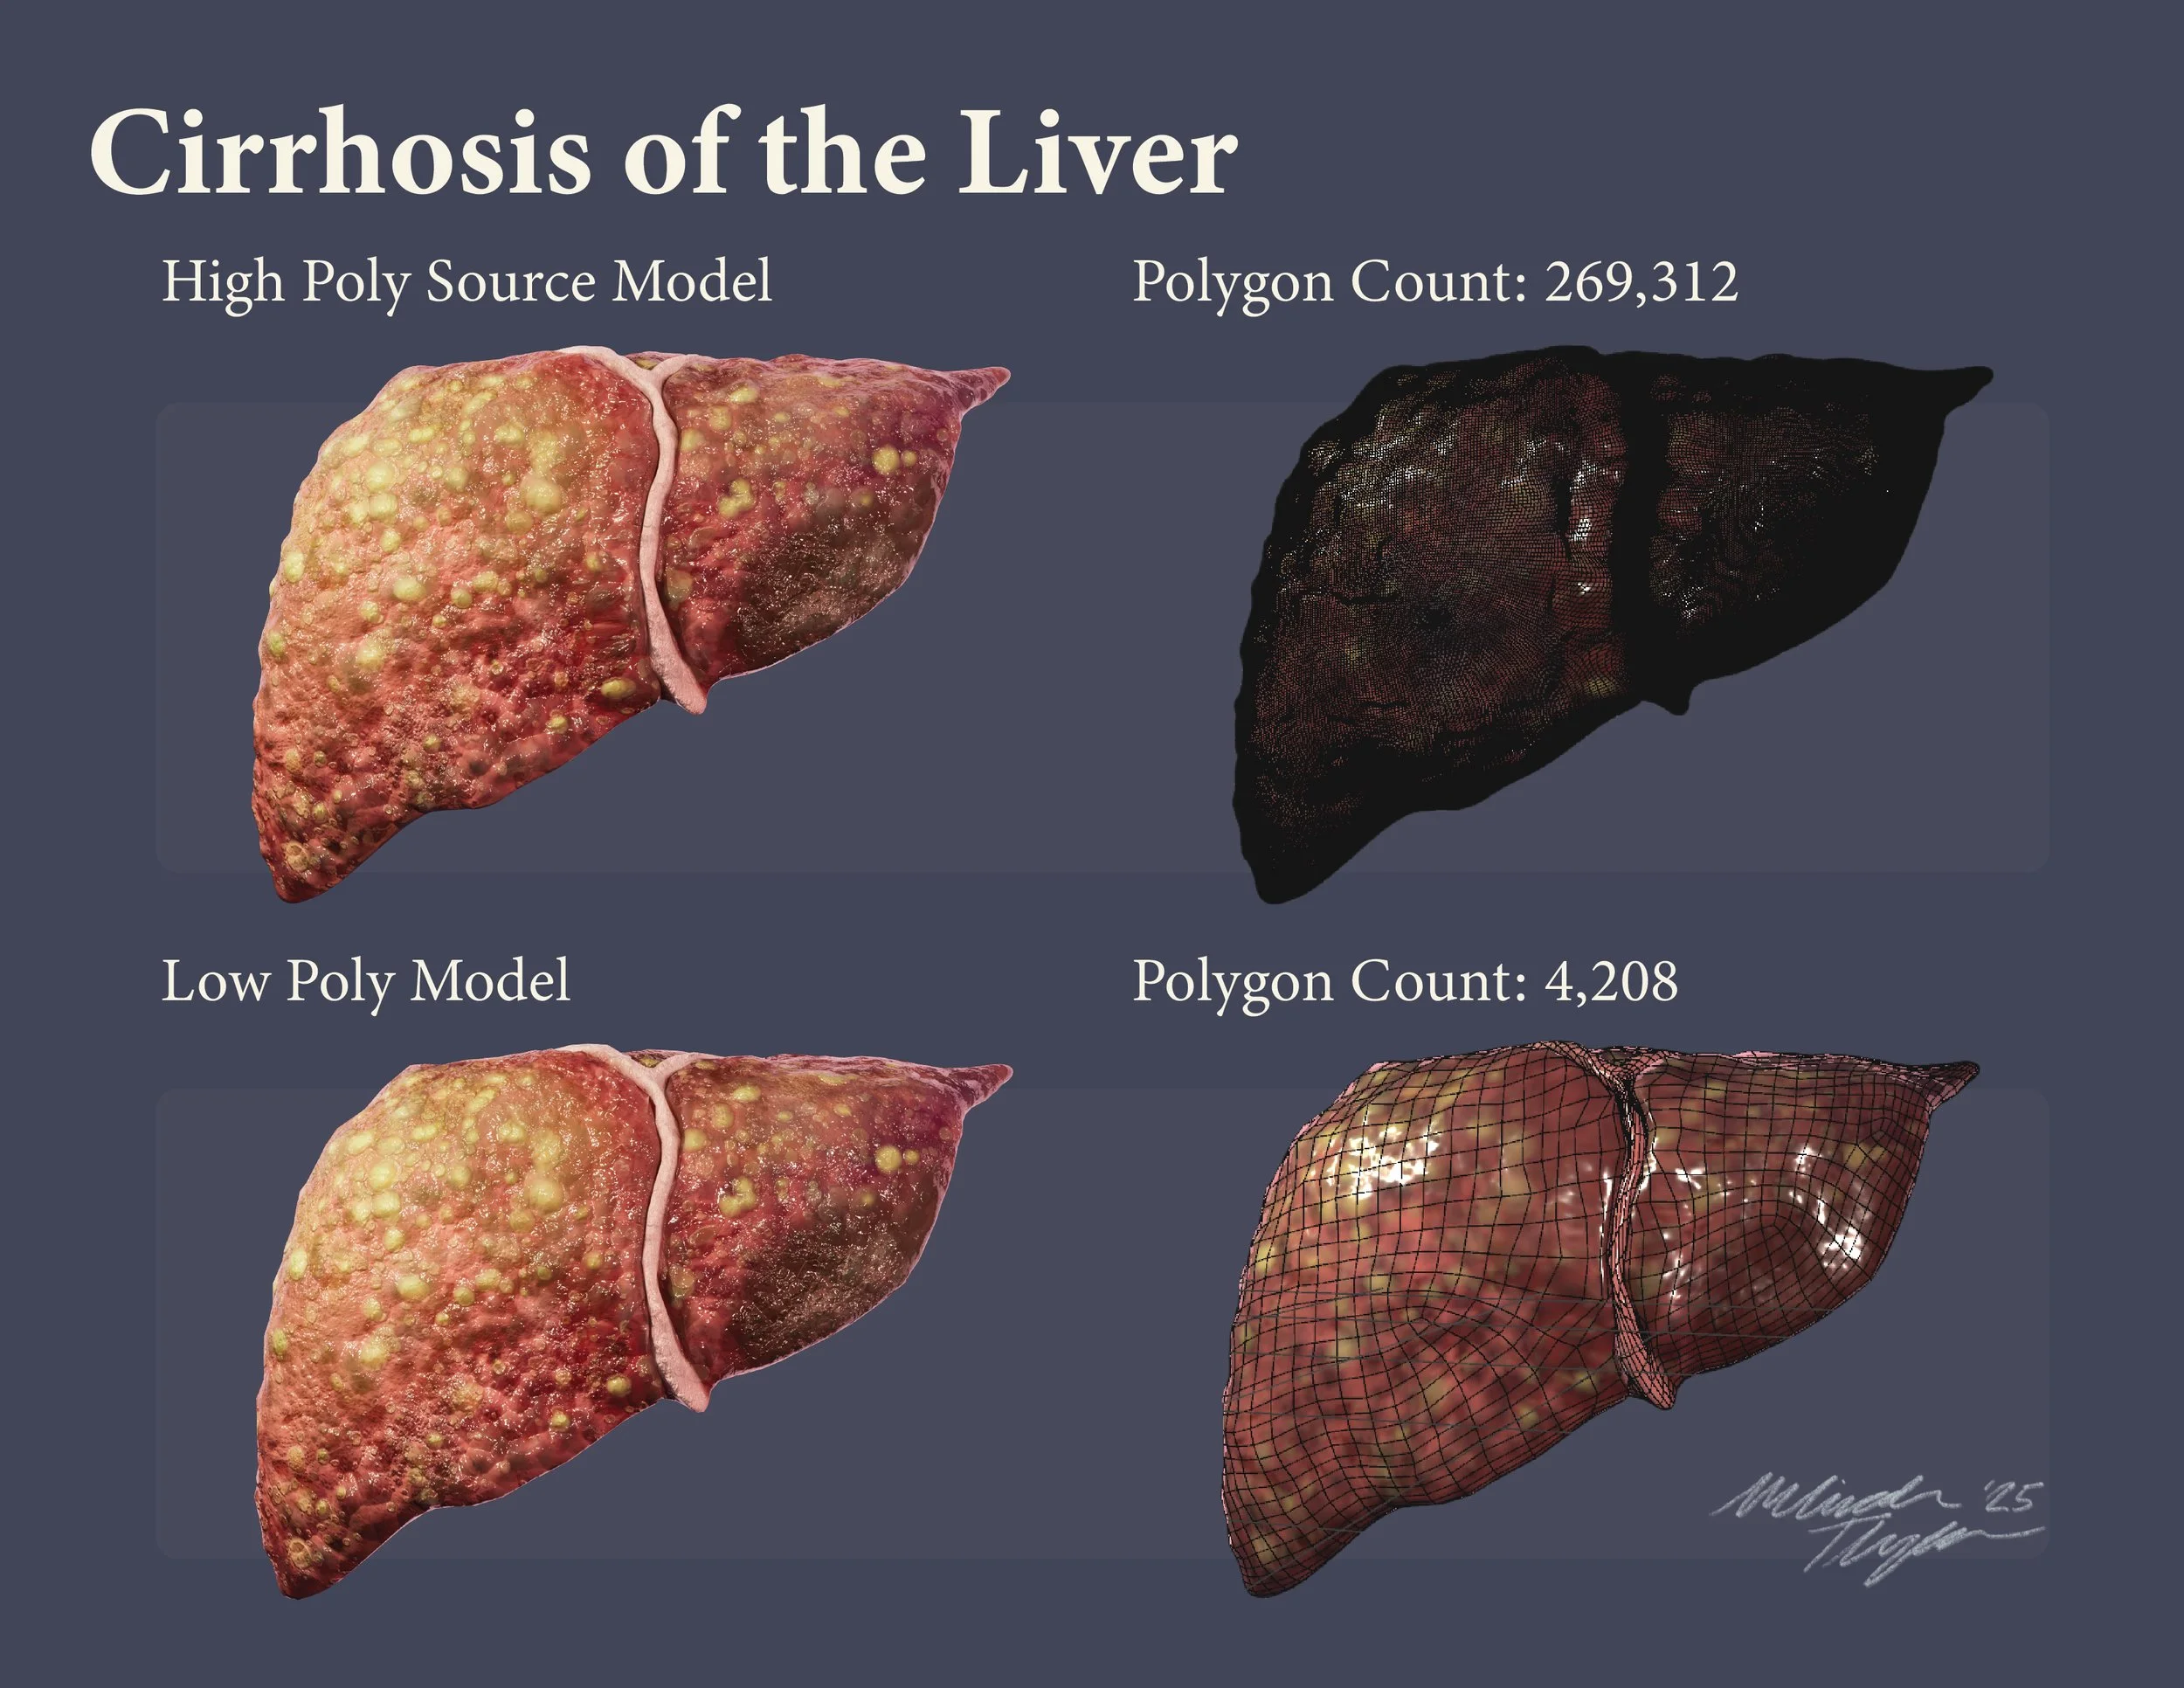

Polygon Optimization: Cirrhosis of the Liver